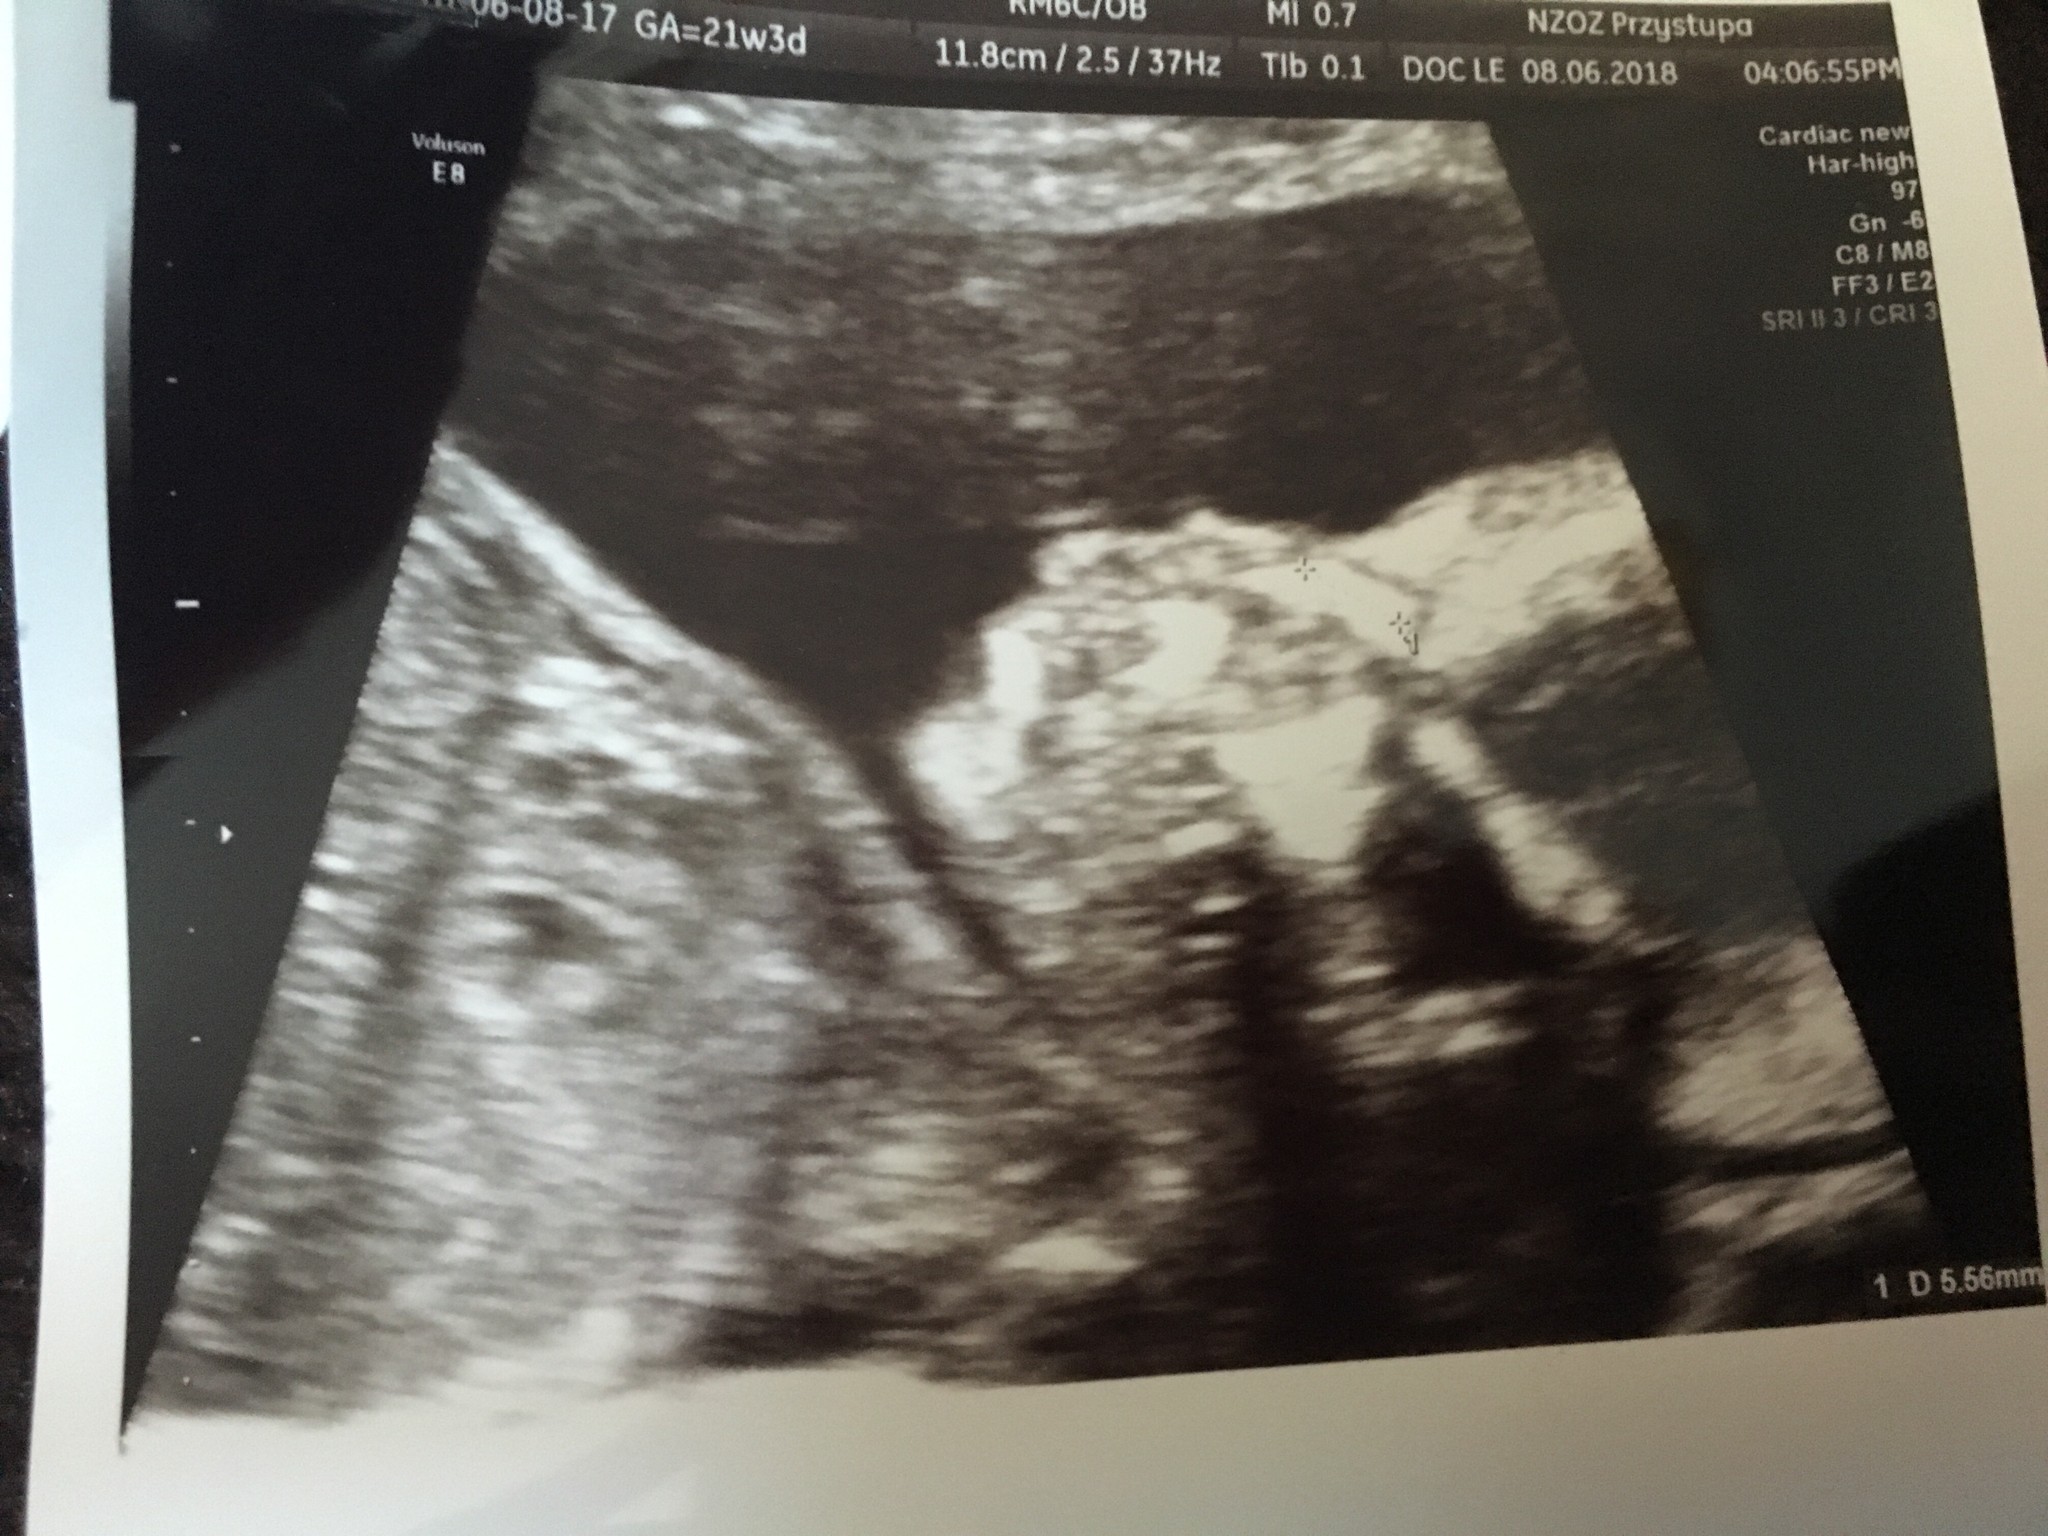

Ja już po badaniu połówkowym. Synek 21+2 z OM waga 447gr, wszystko Ok, posprawdzała wszystko dokładnie i dosyć długo więc jestem zadowolona, zdjęć dostałam chyba z 15 W gabinecie byłam godzinę. Jedyne zastrzeżenie było do długości szyjki 2,67cm. Znowu mam brać luteinę 2*1 i przyjść na kontrole za 2 tyg. Być może dziś miałam taka szyjkę bo spędziłam w aucie 3h i może dziecko tak napierało na ta szyjkę... zobaczymy. Najważniejsze że mały jest zdrowy